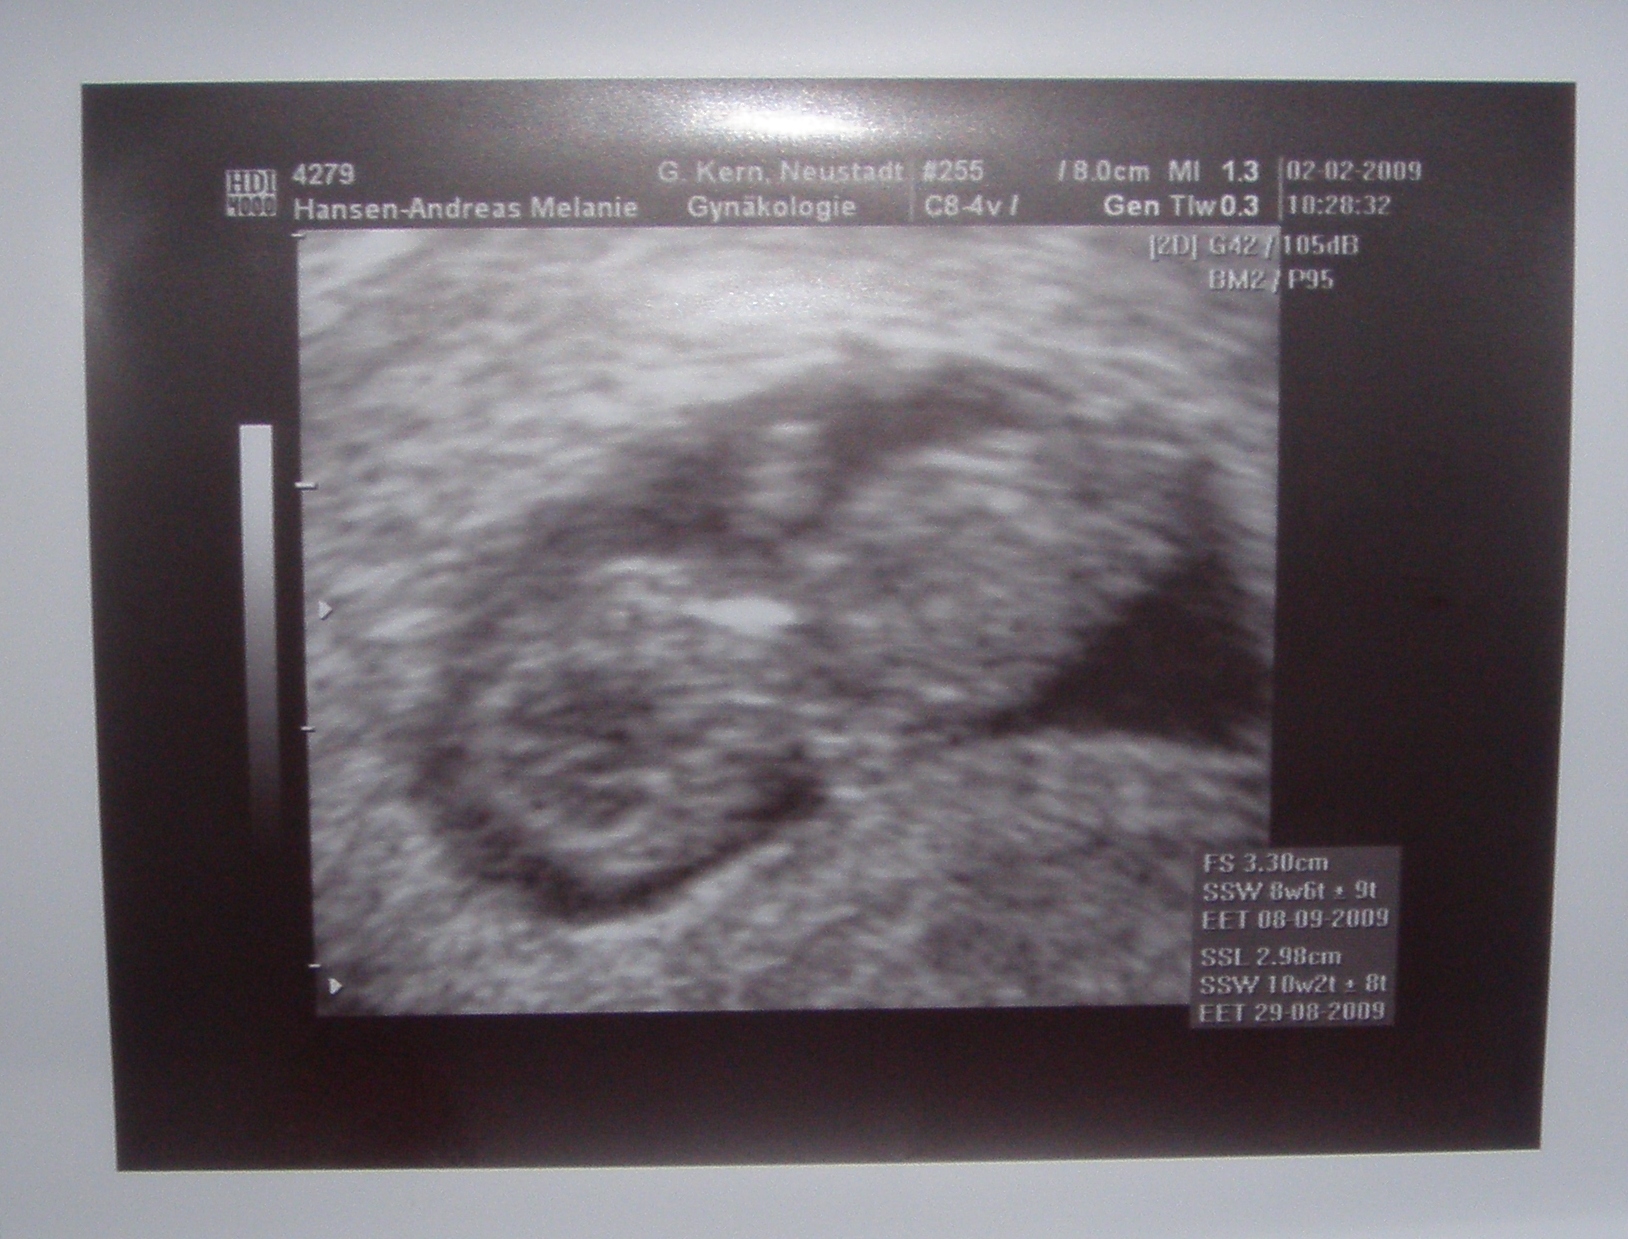

2 Shooting, SSW(7+4): Es ist so beeindruckend. das 10 Tage so viel ausmachen

können. Wie baby wohl am 02. Februar aussieht?!? Übrigens nennen wir unseren

Montag den 02.02.2009: Was für ein

aufregender Tag! Baby war so munter, damit hätte ich nie gerechnet. Es hat

sich ständig gedreht und mit den Fäusten herumgefuchtelt. Men Herz ging

richtig auf wie ich es sah. und gewachsen ist es wieder wahnsinnig. Der Papa

war heute auch mit dabei und ich hab ich selten so stolz gesehen. Das macht

mich auch sehr stolz. Auch gewachsen ist es wahnsinnig. :-D Fast 3 cm groß

und passt kaum noch in die Fruchthöhle. Da werde ich mich wohl in den

nächsten Tagen wieder ordentlich auf Mutterbanddehnungen einstellen müssen.

Anbei das nächste Bild.